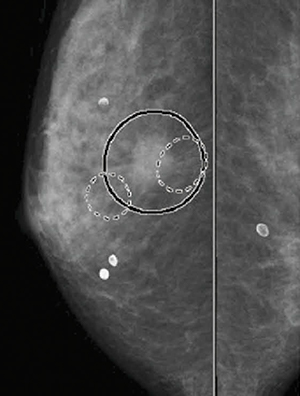

マンモグラフィCAD(computer-aided detection)は,マンモグラフィ画像から,微小石灰化クラスタおよび腫瘤陰影が疑われるエリアを自動的に検出し,画像上にマークで提示することにより読影医を支援する技術です。コニカミノルタのマンモグラフィCADシステム「NEOVISTA I-PACS CAD typeM」(図1)は,検診をはじめとしたマンモグラフィ読影の現場で活用され,「淡く細かい石灰化まで検出できるので安心できる」「長時間読影などで疲労を感じ始めた時に助けてくれる」「病変を覆い隠すことのない『自由曲線で囲む』マーキング表示が見やすい(図2)」などの評価を得ています。

図2 CAD結果のマーキング表示の例